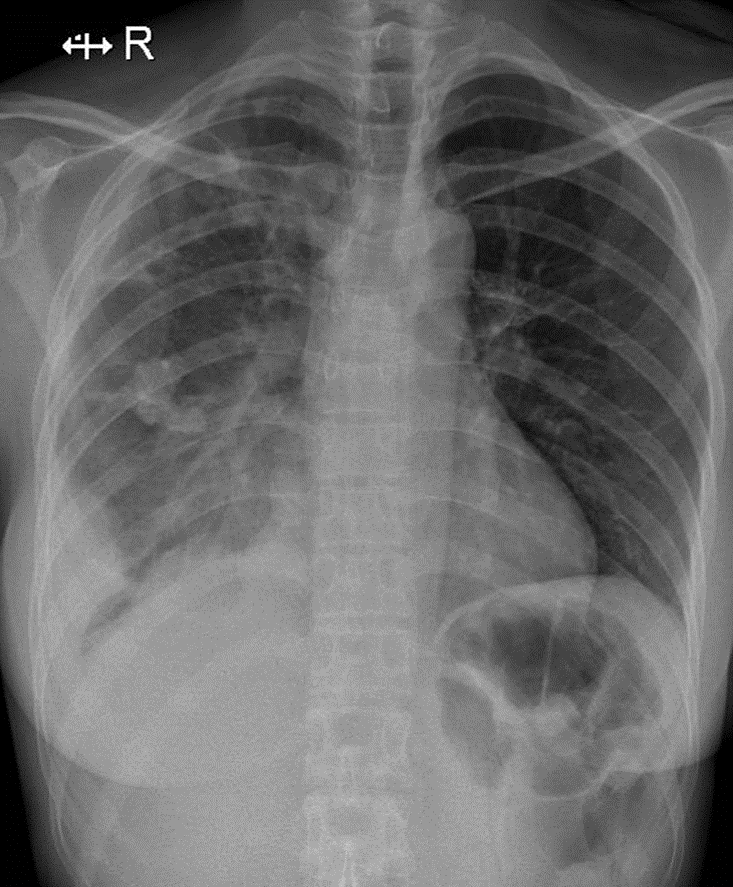

1-Tổn thương phế nang dạng nốt rải rác phổi (P) => Viêm phổi 2-Tràn dịch màng phổi (P)